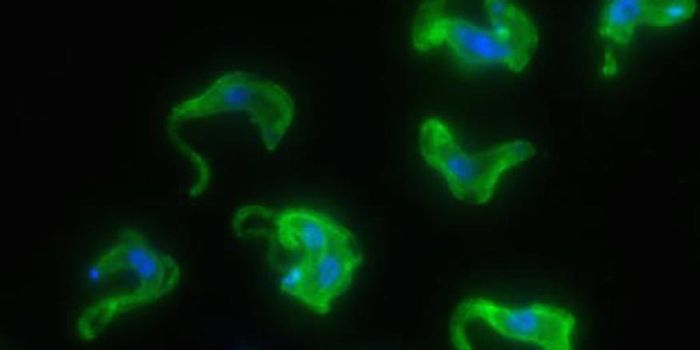

MAR 30, 2016Health & MedicineResearchers claim to have pinpointed the neural stem cells that Zika seems to be targeting. The Zika virus outbrea ...